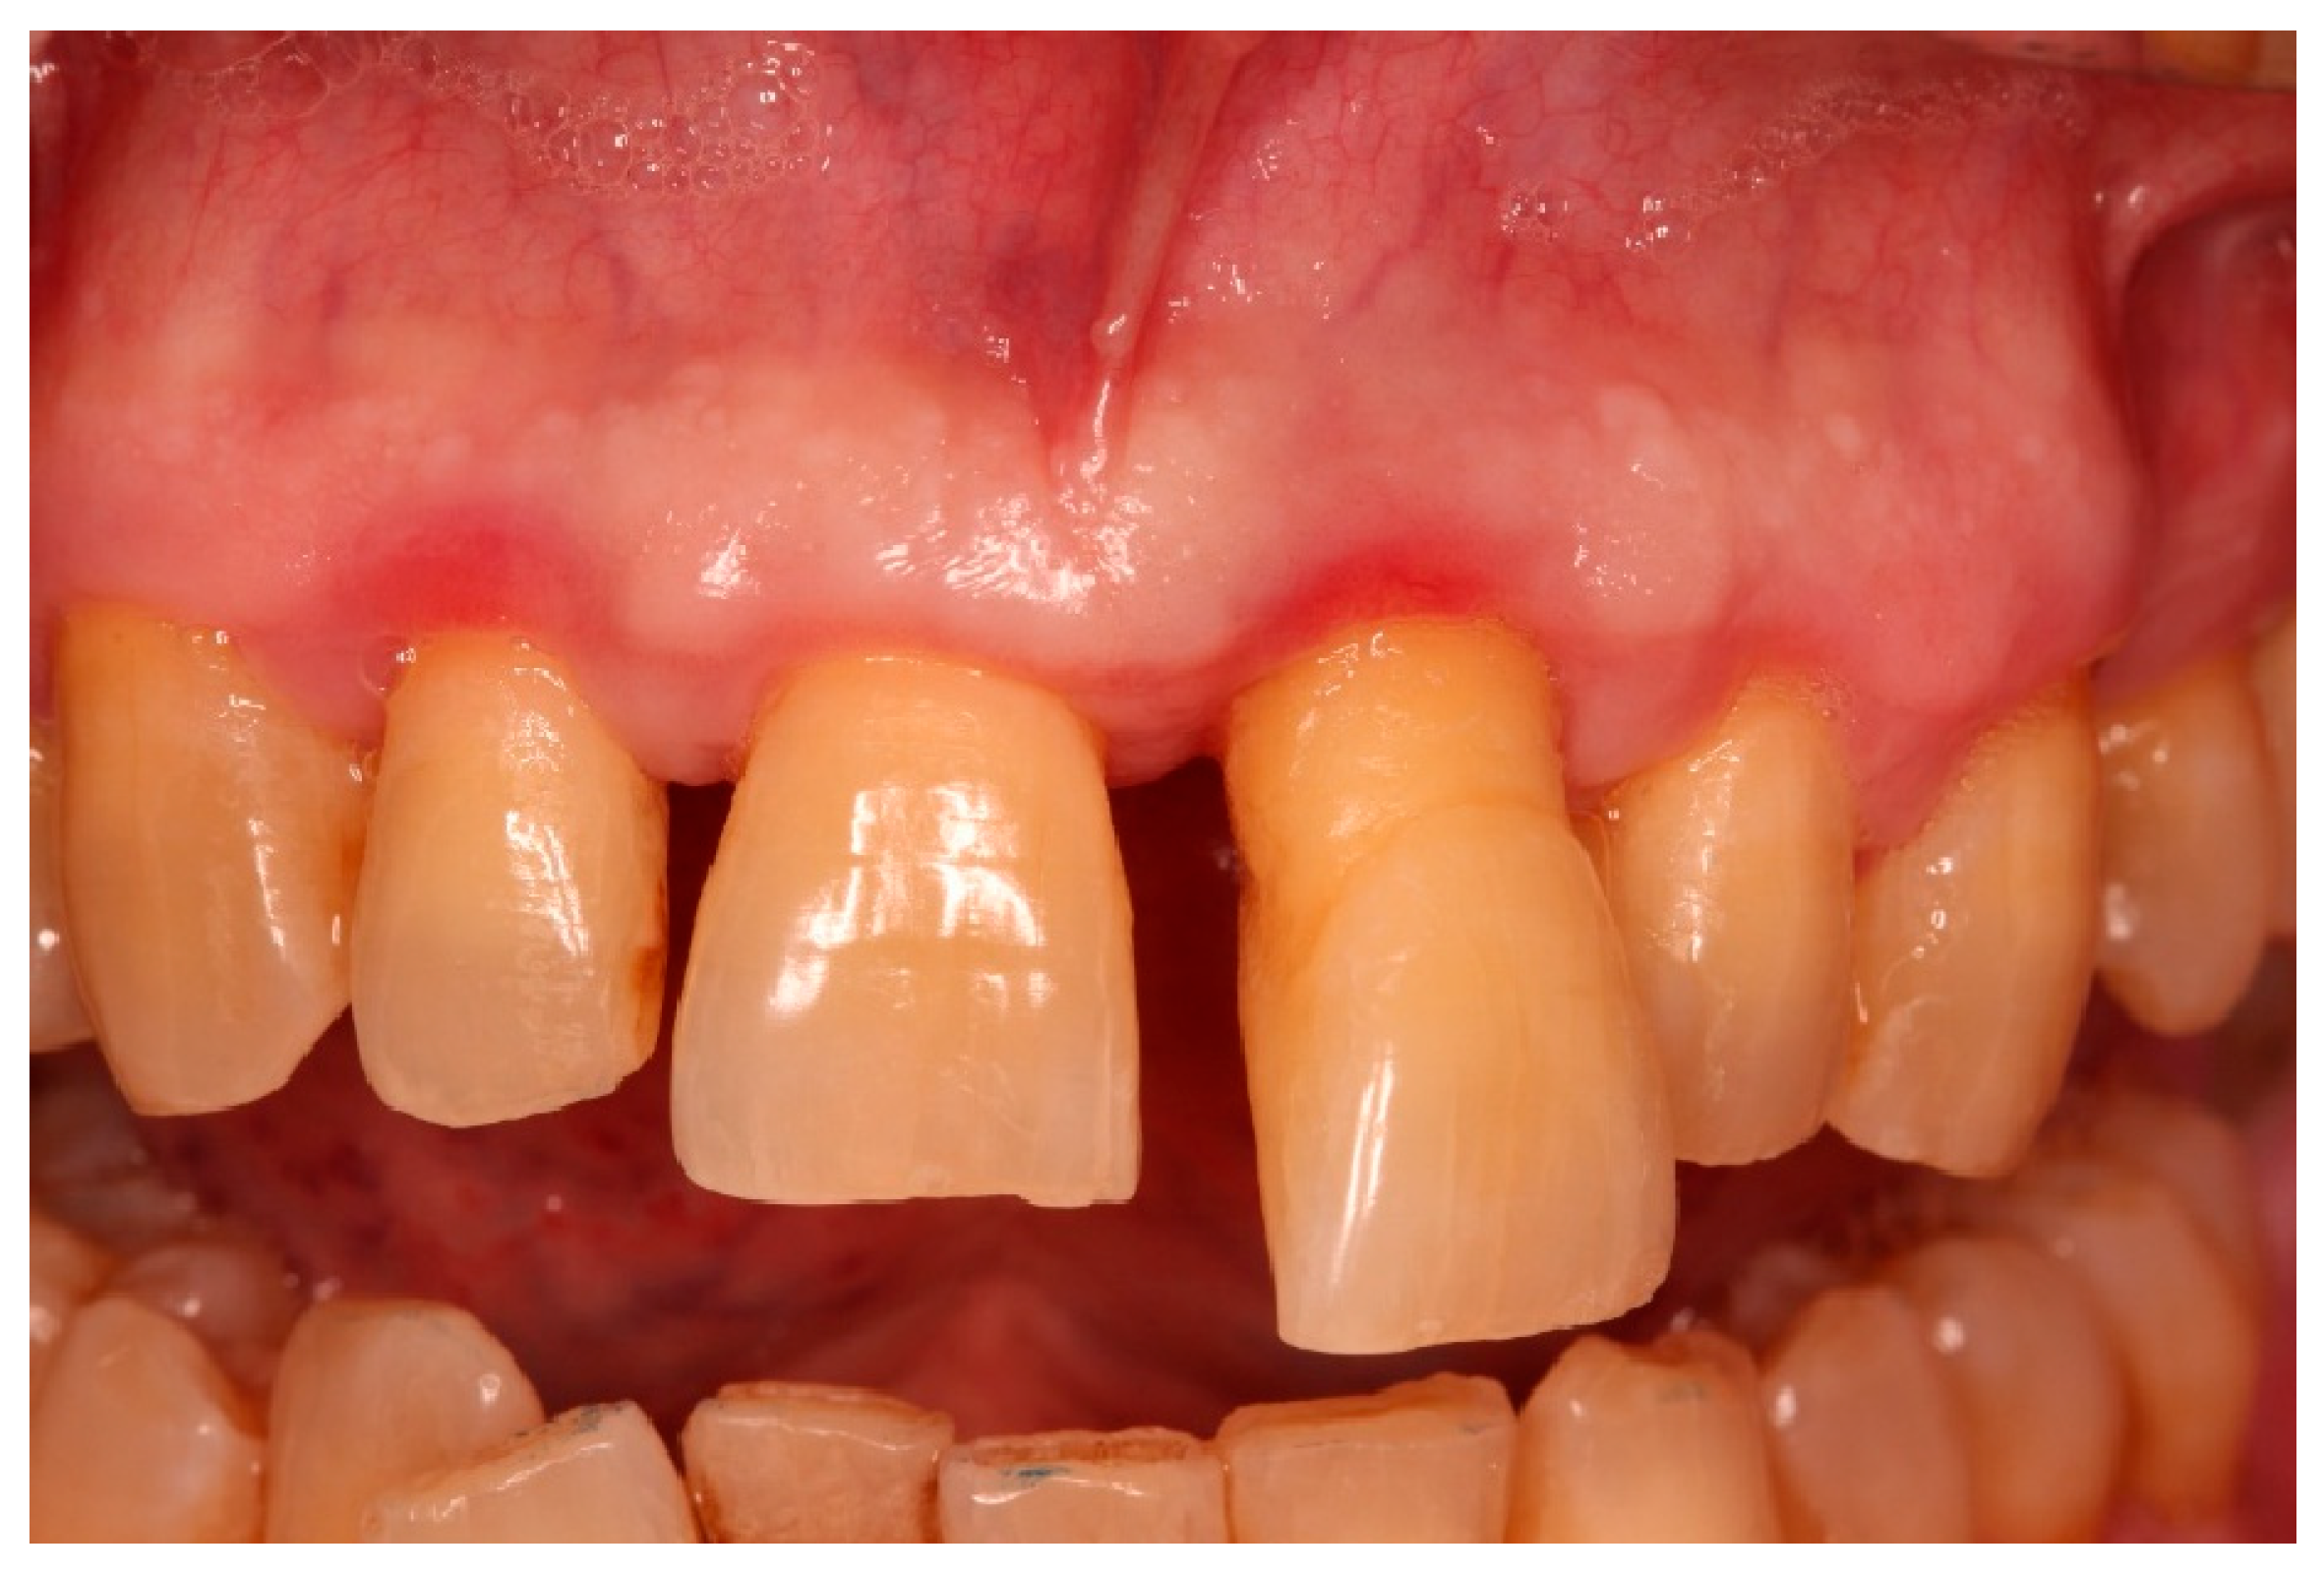

2.2. Patient Information and Periodontal Diagnosis

2.3. Initial Periodontal Therapy